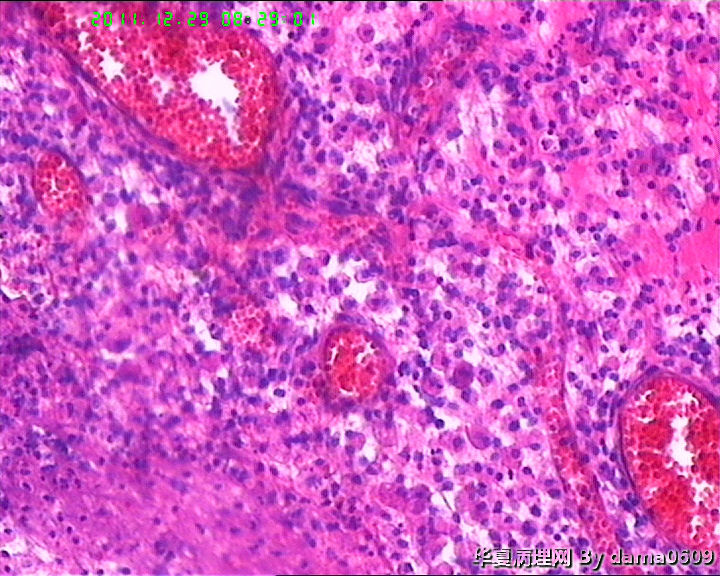

另一为小块囊壁样组织。镜下见卵巢间质内大量淋巴细胞、嗜酸性粒细胞浸润,间质出血。囊壁囊腔一侧见组织细胞、嗜中性粒细胞浸润,小血管增生(图1-9)。局灶见较多的平滑肌组织,内见有异位的子宫内膜组织(图10、11、12)。另于平滑肌组织间见到散在的小腺体(图13~30)。学生不解:1、老年人卵巢内可以出现平滑肌组织,如卵巢门处。此例如此多的平滑肌是正常的吗?   2、平滑肌间的小腺体若是异位的子宫内膜腺体但周围不见内膜间质成分。若非内膜异位腺体,学生又不知如何解释,尤其图19、20、21。请老师们指点迷津。感谢!!

• 感谢老师们一年来的支持,年终岁尾最后一贴,请老师们指教!!图19

图19

• 感谢老师们一年来的支持,年终岁尾最后一贴,请老师们指教!!图20

图20

• 感谢老师们一年来的支持,年终岁尾最后一贴,请老师们指教!!图21

图21